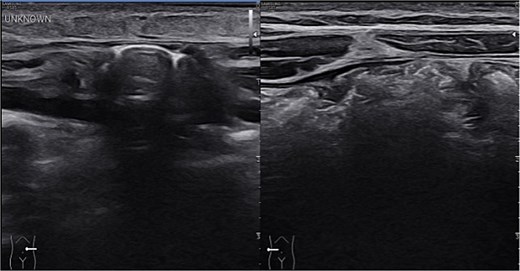

Sonographic imaging of the abdomen revealing a hernia defect (white line) and the hernial sac (white arrows).

Sonographic imaging comparing left and right upper quadrant. On the left side intestinal content is seen within the hernia sac. On dynamic sonography peristalsis was apparent.